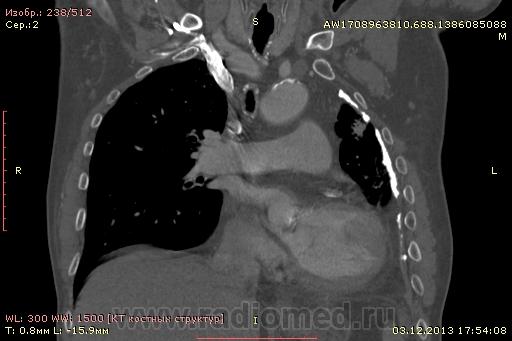

Доброго времени суток уважаемые форумчани! :)Провели исследование КТ грудной клетки с контрастированием, для выявления аневризмы грудного отдела аорты. В результате увидели это:

??? Аневризму честно не вижу (мало опыта в определении аневризм). Тромбоз в бассейне верхней полой вены. В левом легком обызвествленные плевральные шварты? как исход осумкованного плеврита неизвестной давности?

на VRT-реконструкции. плотность до + 1000 HU. видел такое как посттуберкулезные обызвествления плевры, надо завтра ещё раз поговорить с лечащим врачом, может ошиблись

Ребята, вы что, какая жидкость? Чистая известь, посмотрите в костном окне. Отставить натив (в данном случае, хотя для аневризм он обычно нужен). Отставить тромбоз верхней полой вены (потоковые артефакты, не дело вены в артериальную фазу оценивать). Отставить аневризму  аорты, поперчник восходящего отдела на уровне легочного ствола 42мм. А вот легочная гипертензия, здравствуй: поперечник легочного ствола - 37мм, ПЛА - 25мм, ЛЛА - 25мм, НАо - 25-34мм.

Для справки: холестериновые камни имеют плотность менее 100 ед.Н. Имеющаяся хренотень в левом гемитораксе имеет плотность больше костной, до 1500 ед.Н. Вопрос: какая химико-физико-биологическая реакция может способствовать превращению мягинькаво холестерина в термоядерную плевральную лепёшку?)